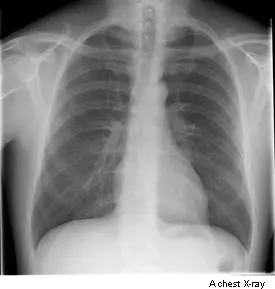

chest x-rays to show fluid, signs of infection, an enlarged heart or tumours in the chest such as lung cancer

You usually have a chest x-ray standing up against the x-ray machine. If you can’t stand you can have it sitting or lying on the x-ray couch. For x-rays of other areas of the body the best position is usually lying down on the x-ray couch.